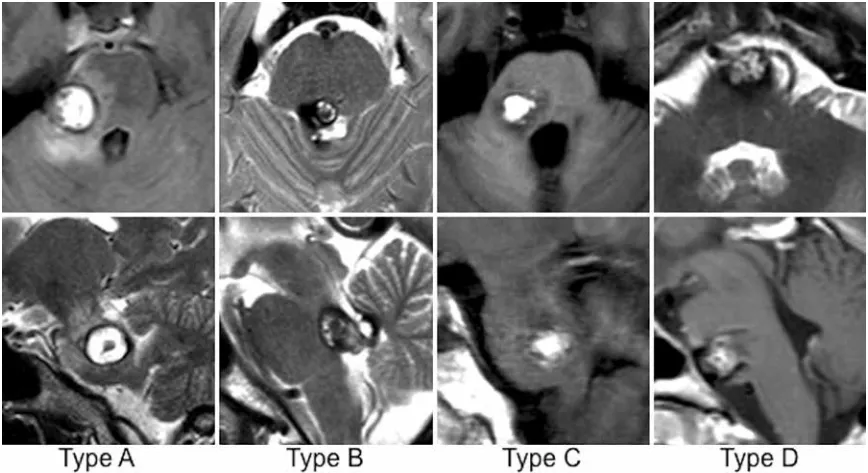

多年來,神经外科医生持续寻找更安全的手术通道。INC巴特朗菲教授在本研究中根据最合适或可能的手术入路定义4种不同病变类型(A-D型)脑桥海绵状血管瘤。

每列显示一名具有代表性脑桥海绵状血管瘤类型患者的轴向(上)和矢状(下)MR图像。

A型病变

病灶贴附脑桥外侧,只能从侧面切除(后外侧入路),从中线切入可能损伤脑干。

B型病变

病灶靠近脑桥后方的菱形窝(第四脑室底),只能从中线切除(后内侧入路)。

C型病变

病灶位于外侧和中间之间,两种入路均可切除(本研究核心对象)。

D型病变

病灶生长在脑桥前面,需从前方绕行进入(前外侧入路)。

最引人关注的C型病变既可从后外侧也可从后正中入路处理,占所有患者的57%。